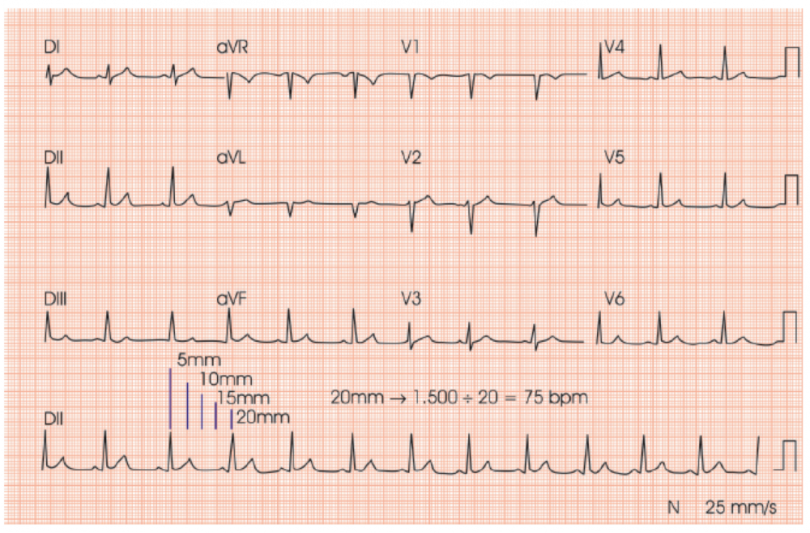

A forma mais precisa para calcular a frequência cardíaca (FC) no ECG é também trabalhosa. Para isso, podemos dividir 1500 pelo nº de milímetros entre 2 complexos QRS (intervalo R-R). Utilizamos esse número porque, como a velocidade padrão do papel no eletrocardiograma de 25 mm/s, em 60 segundos (ou 1 minuto), seriam percorridos 1.500 mm. Exemplo:

Bem, isso não parece ser muito prático para usar no dia a dia. Não teria uma opção mais simples? Sim, há.  Uma opção mais rápida para a prática é dividir 300 pelo número de quadrados (de 5mm) entre os R-R no ECG.

Assim, uma distância entre o R-R de 2 quadrados (que seria 10mm) representaria uma FC de 150bpm; de 3 quadrados, 100bpm; de 4 quadrados, 75bpm; de 5 quadrados, 60bpm, e assim por diante.

No traçado acima, por exemplo, como a distância entre o R-R é de aproximadamente 4 quadrados (de 5mm cada), visualmente saberíamos que a FC estaria bem próxima de 75bpm.